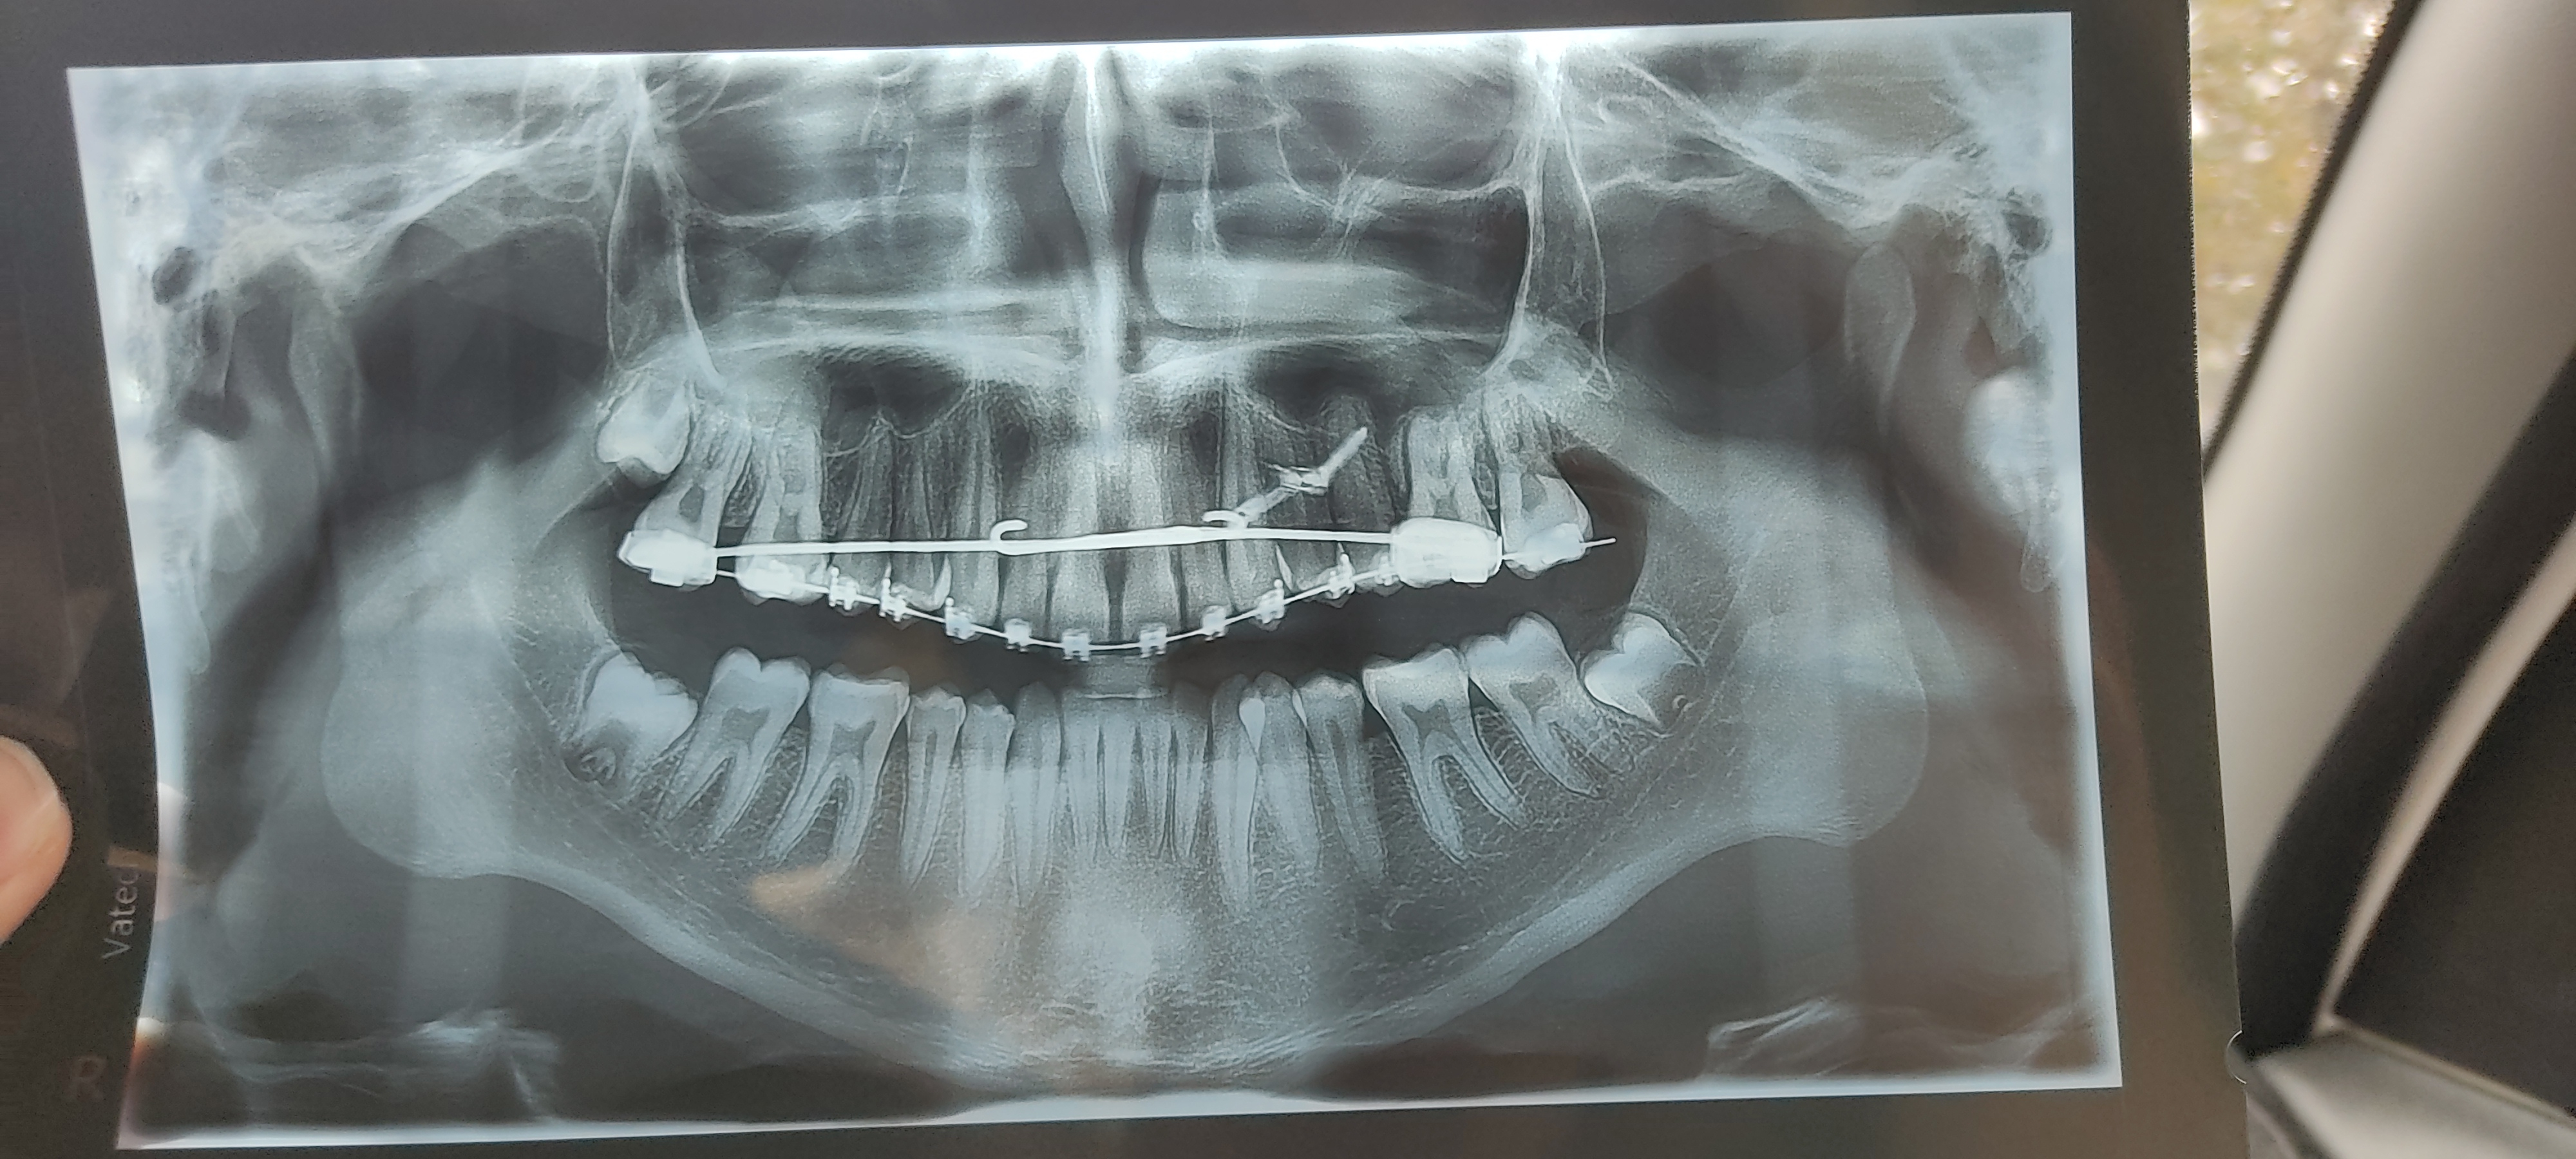

Loads of people tell me I have exaggerated bone density when that really isn't the case.

View attachment 5829View attachment 5830

Like holy shit, dude, next to this guy I look like a boneless twink.

I know bonesmashing is cope, but seeing shit like this just makes me want to fucking swell my whole face up, even if it's only temporary.